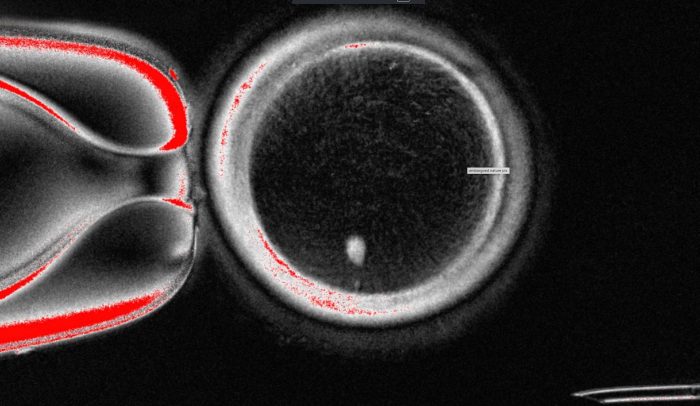

The OHSU team removed the nucleus from a human egg cell and replaced it with the nucleus from a human skin cell. But a skin cell contains two sets of chromosomes, and eggs and sperm are supposed to each contain only one set that combine during fertilization. The researchers therefore induced the egg-like cells to discard extra chromosomes, injected donated sperm and jumpstarted post-fertilization development.

About 9% lasted for six days in lab dishes, reaching the blastocyst stage of early embryo development, before the experiment was stopped.